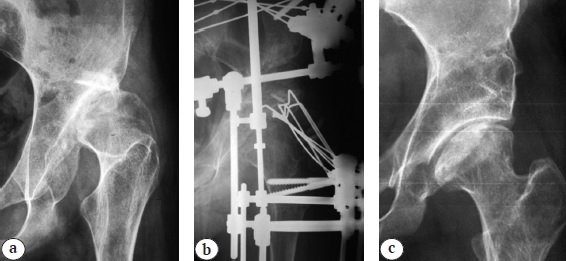

Figure 1 presents a sample case from group 1.

Fig. 1. X-ray images of a 14-year-old patient; dysplastic coxarthrosis, stage II; dislocations, stage III: a — before treatment; b — during treatment; c — 7 years follow-up